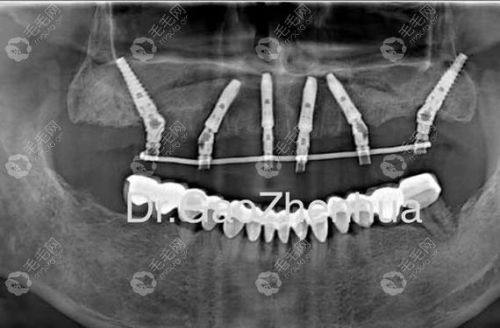

种植牙:主推奥齿泰种植体,可开展all-on4、穿颧穿翼等高难度种植手术,复杂手术通常40分钟左右即可完成

买院长:擅长种植牙领域,可开展all-on4、穿颧穿翼等高难度种植手术,临床经验多